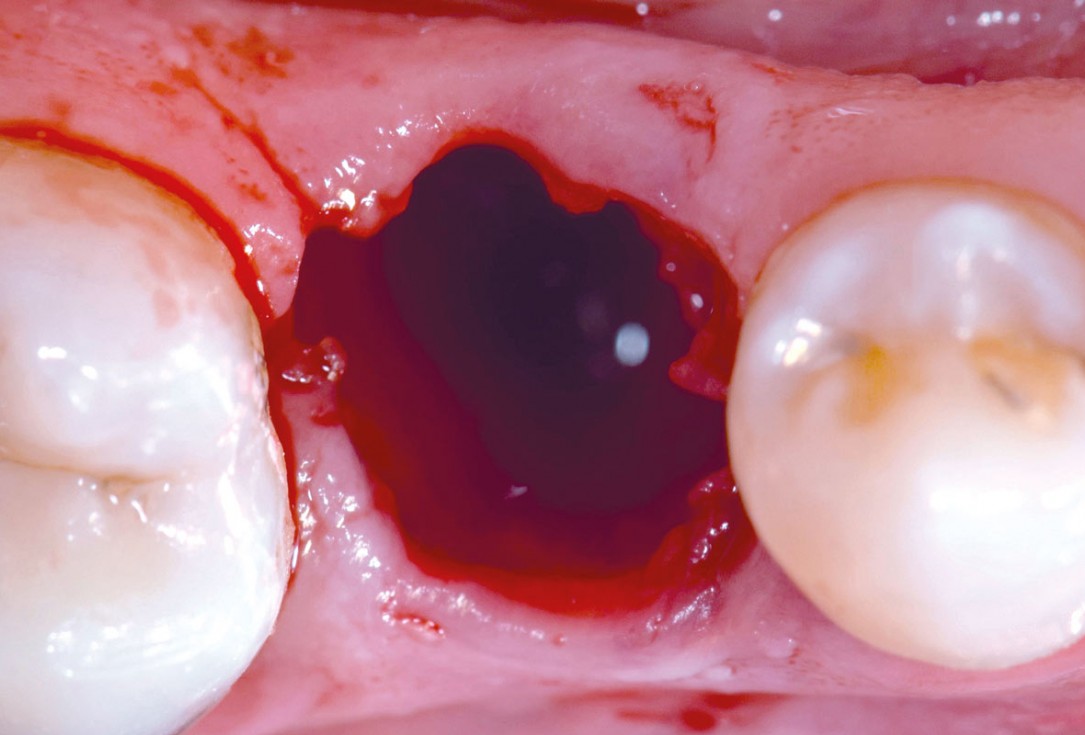

4/17 - Atraumatic tooth extractionApplication of mucoderm® for soft tissue management around single implants at second stage surgery Dr. C. De Annuntiis